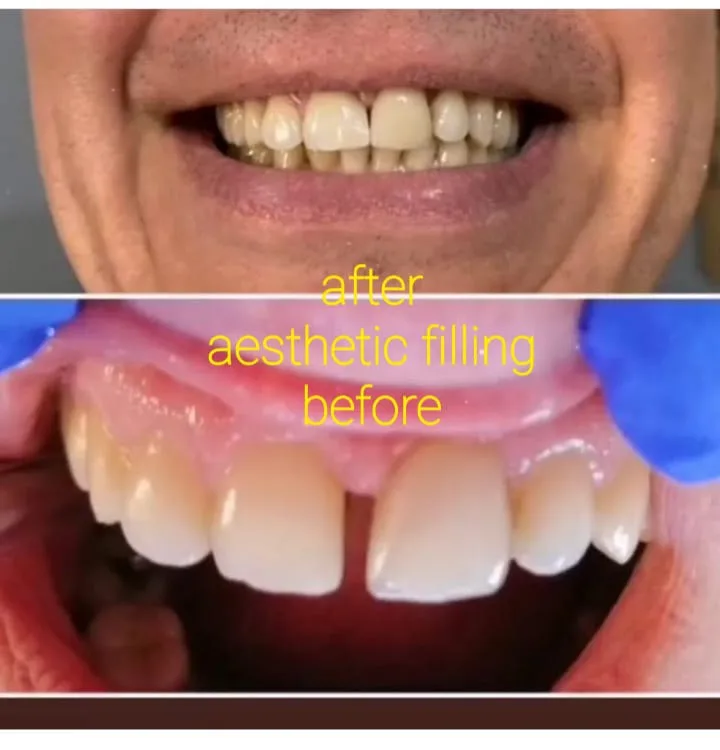

✅ Dentisterie esthétique: blanchiment et restauration des dents